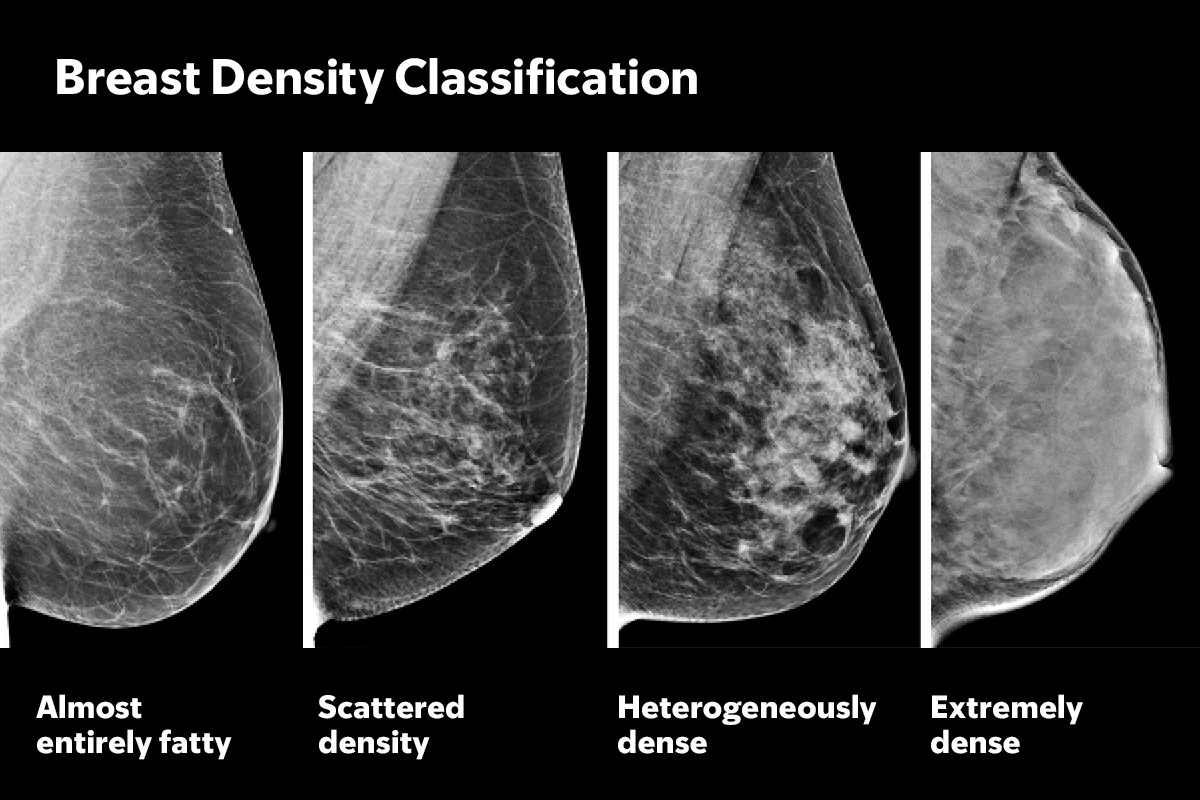

Při mamografii se ukazuje velký problém. Žlázová tkáň je na snímcích bílá. Rakovinotvorné nádory? Ty jsou také bílé. Pokud máte hodně žlázové tkáně (hustá prsa), je to jako hledat sněhovou vločku ve sněhové bouři.

Lékaři tomu říkají „hustota prsou“ a vůbec to nesouvisí s tím, jestli kupujete podprsenky ve velikosti B, nebo DD. Je to poměr tuků a žláz.

- Tuková tkáň (Ta, co neškodí): Na mamografu tmavá až černá. V ní je snadné vidět bílý nádor.

- Žlázová tkáň (Ta, co maskuje): Na mamografu bílá, což může rakovinu spolehlivě zamaskovat. Aktivuje se po porodu a s věkem má tendenci ubývat (ale ne u každé).